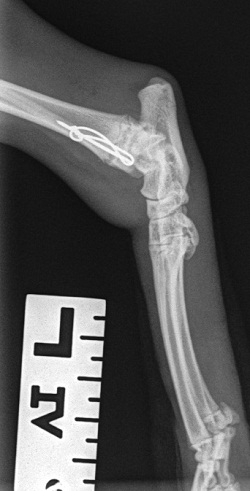

Feline lateral maleollar (distal fibular) repair using a 0.7mm pin and wire